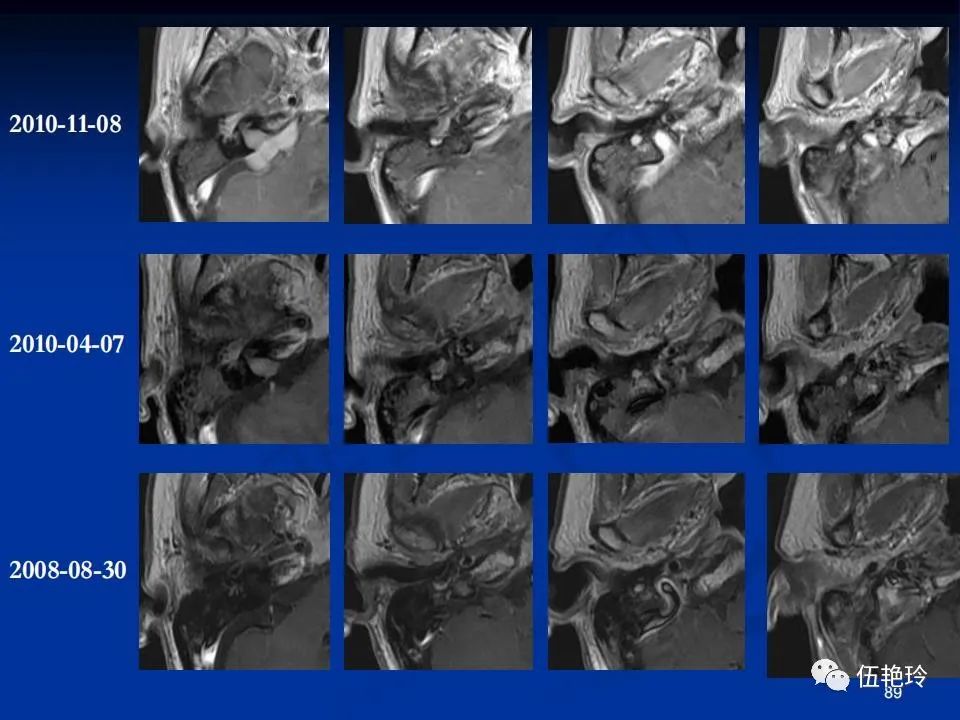

耳与面神经的解剖